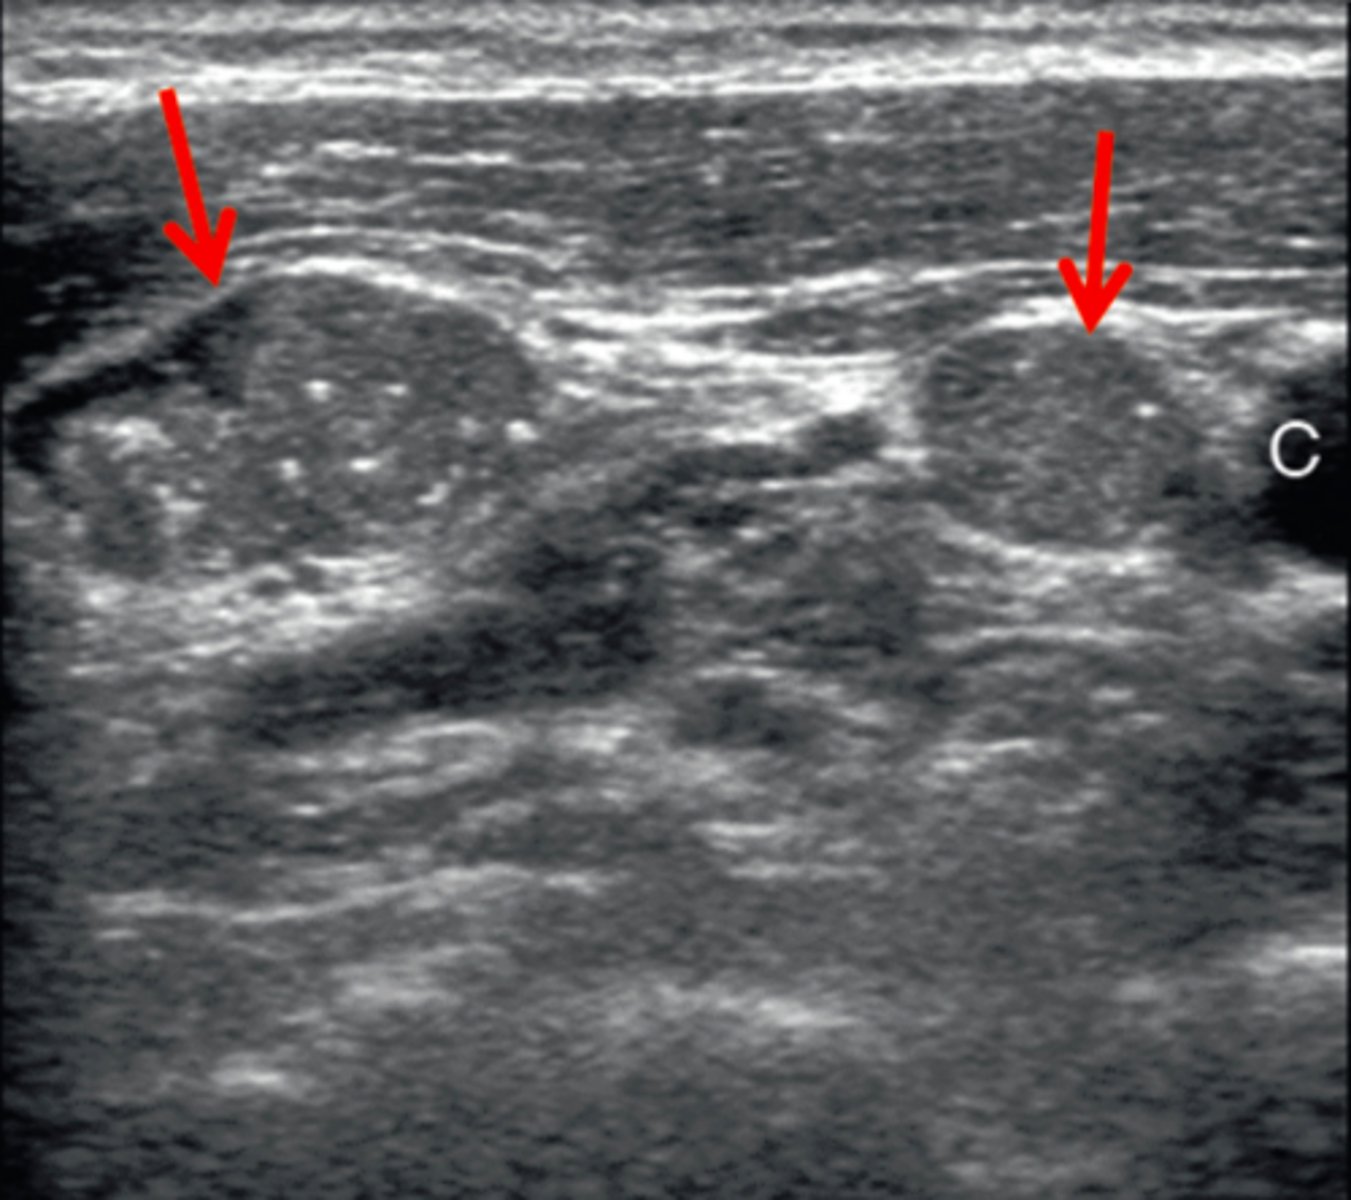

11. The structures identified by the arrows in Figure 12-26 were discovered in the lateral neck of a patient with a history of thyroidectomy due to papillary carcinoma. What do these structures most likely represent?

a. Parathyroid adenomas

b. Parathyroid cystadenomas

c. Metastatic disease within lymph nodes

d. Normal lymph nodes